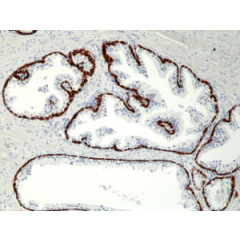

anti-Cytokeratin-19 (human), Rabbit Monoclonal (RM364)

anti-Cytokeratin-19 (human), Rabbit Monoclonal (RM364)

REV-31-1249-00 REV-31-1249-00-R100 100 µl CHF 468.00